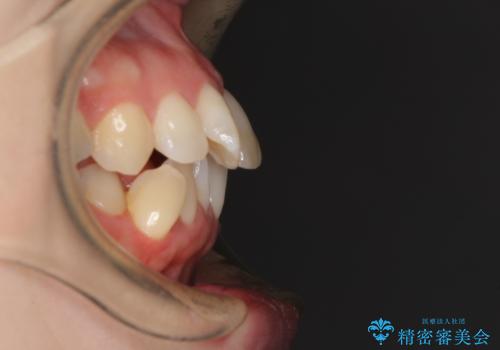

口元の突出感とデコボコがあり、上下左右の小臼歯4本を抜歯して矯正治療を行う方針としました。(右上は欠損のため計3本抜歯)

むし歯となっている歯は状態が悪く、将来的に抜歯となる可能性が高かったため、定石で抜歯させる小臼歯の代わりにむし歯となっている大臼歯を抜歯し、ワイヤー装置にて矯正治療を行うこととしました。